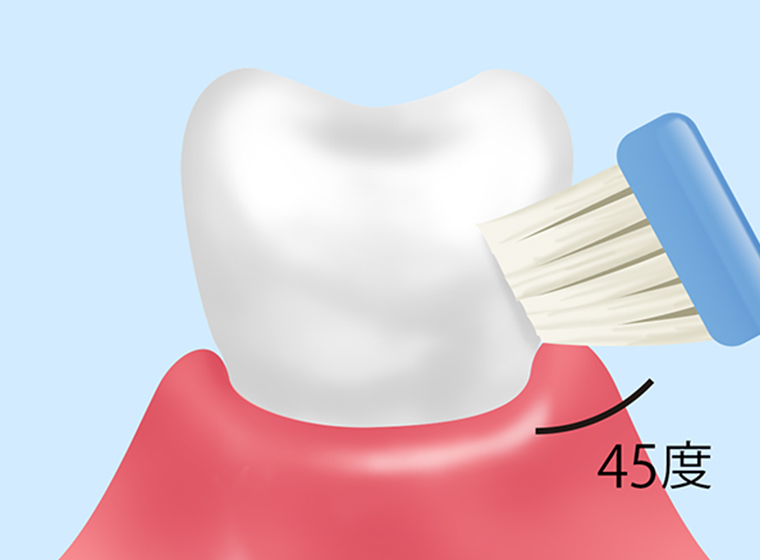

ブラッシング指導

|

歯周病の治療や予防の基本は歯の汚れをきちんと落とすことです。そのために患者様のお口の状態にあったブラッシング方法をアドバイスいたします。初期の歯肉炎に対して行う治療法です。 |

ブラッシング指導

むし歯や歯周病の予防の基本は毎日のブラッシングです。しかし自己流のブラッシングでは汚れを除去できません。当院の歯科衛生士が患者様のお口の状態に合わせたブラッシング方法を丁寧にアドバイスしますので、効率よくお口の汚れを落とす習慣を身につけましょう。